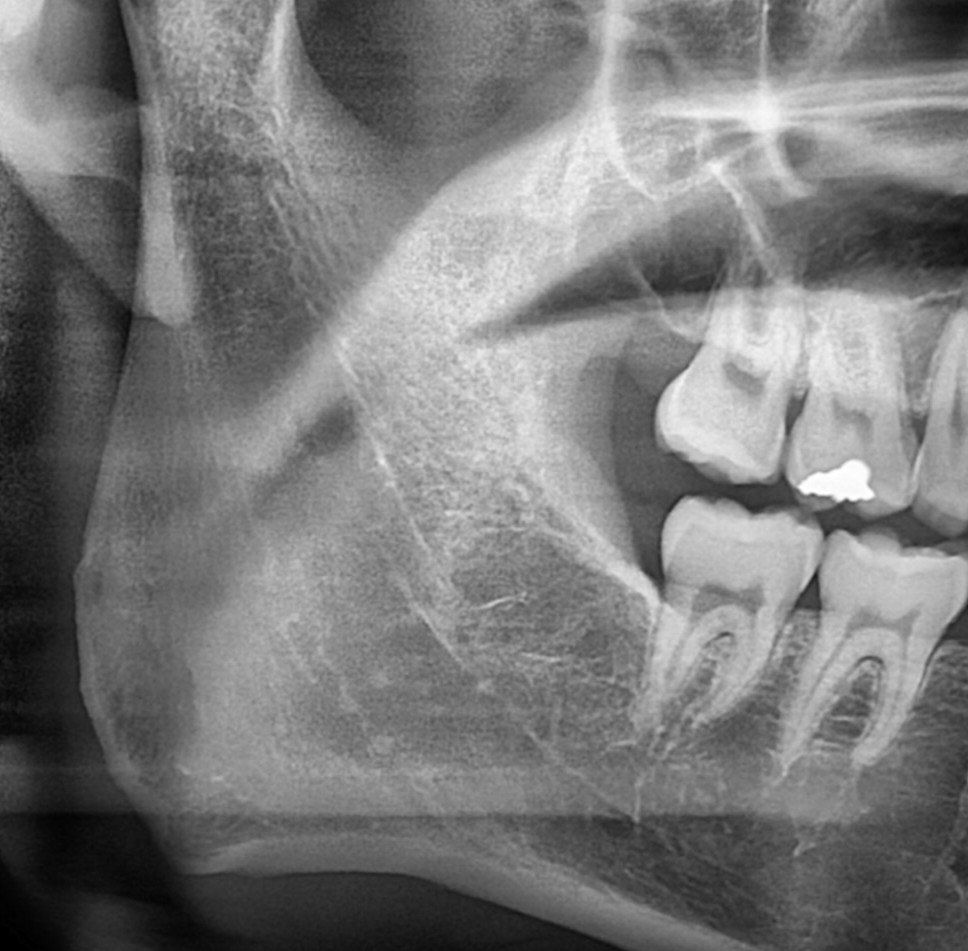

안녕하세요 제가 왼쪽 아래에 큰 사랑니가 있는데요, 맨 끝 어금니 뿌리와 닿아있어 계속 놔두면 뿌리 흡수가 염려되는 상황입니다..그런데 인터넷 검색하다보니 어금니를 발치하는 상황이 올 경우 교정혹은 이식해서 사랑니로 그 자리를 대신하는 경우가 있더라고요, 제 경우도 그렇게 대신할 수 있는건지 여쭤보고 싶습니다..만약에 안 된다면 오른쪽이나 왼쪽 어금니 다른 부위는 그렇게 대신하는게 가능한지 여쭤봅니다..

• 1번 째 사진

사진으로 보이는 부위는 오른쪽 부위이기 때문에 정확한 치아의 관계를 판단하기 힘드나 어금니를 발치하고 사랑니를 어금니 처럼 사용하기 위해서는 교정치료가 필요할수 있습니다.

1. 올리신 방사선 사진은 말씀하신 왼쪽 부위가 아닌, 오른쪽 부위에 해당하는 방사선 사진입니다.(사람의 정면 사진은 바라보고 있다고 생각하시고 방향을 생각해보시면 좌우가 반대입니다)

현재 올려주신 사진으로는 알 수 없습니다. 오른쪽 사진을 올려주셨는데, 여기엔 사랑니가 없습니다.

사랑니가 매복되고 기울어져있는경우, 그 앞의 치아의 뿌리를 흡수시키거나, 충치를 유발하는 경우는 있습니다.

하지만, 앞의 어금니를 빼고 그자리를 사랑니로 대체하기 위해서는, 사랑니가 기울어지지않고 정상적으로 맹출되었을 경우에 가능합니다.